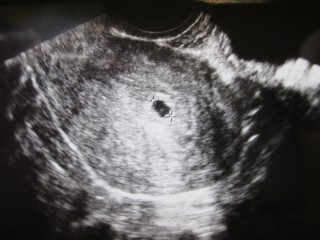

まだ心拍は確認できていない状態です。 胎嚢は8.9mm(真ん中の+‥+で測られているもの)でそのわきに2つほど出血の跡があります。 出血が体外に出てきたらすぐに病院に来るように言われました。 幸い現在6W0Dですが出血はありません。